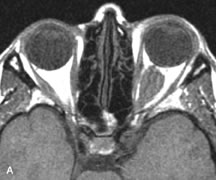

On MRI, uveal melanomas have a typical appearance that helps to differentiate them from other primary and secondary intraocular tumors as well as choroidal detachments. Pigmented melanomas are hyperintense on Tl-weighted images, hypointense on T2-weighted studies, and hyperintense on proton density–weighted examinations (Fig. 24).30,31,50,80–82 These signal characteristics have been attributed to the paramagnetic properties of melanin because of stable free radicals that shorten the T1 and T2 relaxation times. Moderate enhancement is seen on postgadolinium T2-weighted images. Gadolinium-enhanced T1-weighted images are particularly sensitive in detecting choroidal melanomas.83 MRI may be less sensitive in detecting extrascleral extension of tumor than echography performed by an experienced ultrasonographer.84

Fig. 24. A. T1- and (B) T2-weighted MR scans demonstrate a small nodular intraocular mass (arrows) that is very hyperintense on the T1-weighted scan and hypointense on the T2-weighted image. This signal intensity pattern is due to the presence of free radicals within melanin granules. C and D. Postcontrast fat-suppressed T1-weighted scans demonstrate homogeneous intense enhancement of the lesion and no evidence of seleral penetration or optic nerve invasion.